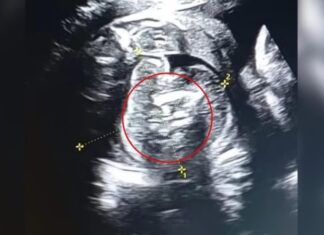

Médicos descobrem que recém-nascido carregava dois fetos no abdômen

Uma mulher indiana de 32 anos foi surpreendida na 35ª semana de gestação ao descobrir que seu bebê carregava dois fetos dentro do abdômen....